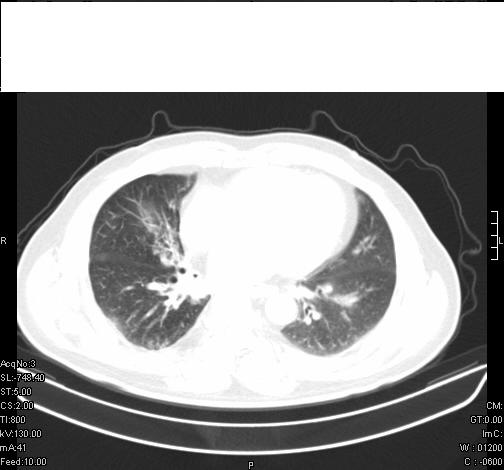

前几天,发了患者的平扫片,患者抗炎一周后增强扫描。右中叶病灶吸收明显,但下叶病灶未见明显吸收。右肺门可见结节影,看来凶多吉少

右肺下叶支气管管腔狭窄,管壁增厚,右下肺见斑片状高密度影,考虑右侧肺门中心肺癌伴阻塞性肺炎

右肺下叶散在的斑片状致密影,下叶支气管变窄。考虑:右肺慢性炎症。

第18幅,好像不能简单用炎症解释,前几天我发平扫时,90%人支持肺癌,现在好像大家更倾向于炎症了,我觉得还是不能排除肺癌。

右肺下叶支气管壁不规则增厚,右肺下叶有斑片状影分布。考虑右肺中央型肺癌伴右肺下叶阻塞性改变。建议支纤镜检查。平扫比增强较好显示了病变情况。

右主支气管狭窄,管壁增厚。考虑右中心性肺ca伴阻塞性肺炎。

既然抗炎治疗有效,可继续治疗;右肺下叶支气管管腔狭窄,管壁增厚,右下肺见斑片状高密度影,右侧主支气管后见结节影(淋巴结?),肺癌不能排出。